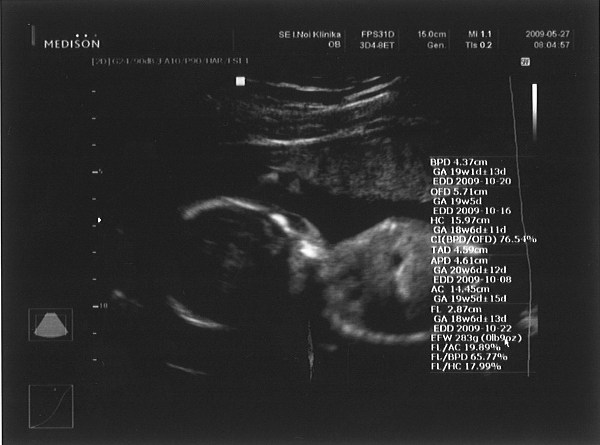

Ja, kisfiunk lesz:

Kép